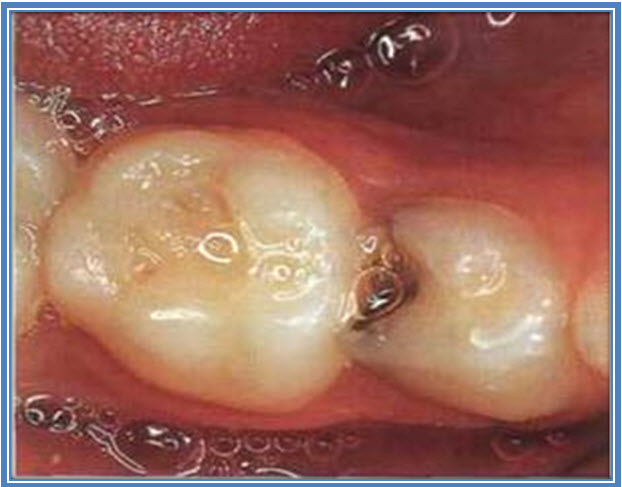

Slika 2. Karijes zatvoren ART metodom bez bušenja